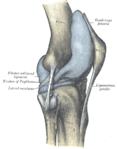

وتتصل عظمة الفخذ والظنبوب (عظمة الساق السفلى الكبيرة) بثلاث طرق هي : 1 – بالأربطة (أنسجة قوية شبيهة بالوتر)، 2 – بالعضلات، 3 - بمحفظة زليلية. وتحيط المحفظة الزليلية بالمفصل. وأربطة الركبة هي الموصلات الأقوى بين عظمة الفخذ والظنبوب. وهذه الأربطة تمنع العظمات من التزحزح عن مكانها.